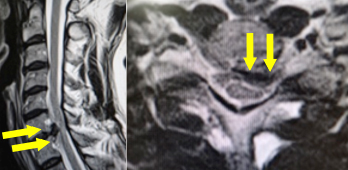

前方から圧迫因子となっている椎間板や骨を取り除き、代わりに腸骨などの自家骨や人工骨、もしくはスペーサーなどを挿入して、障害部位の可動性を止めることで神経症状の改善が見込まれます。前方からの圧迫因子が大きい場合、不安定性がある場合、後弯と言って骨の並びが後ろに弯曲している場合には有効な手術法となります。近年では、金属製のプレートとスクリューなどで早期離床が可能となっており、通常、手術翌日より座位や歩行訓練を行います。術後は、頚部を固定する装具を約1−3カ月装着します。

手術前のMRIでは、第6/7椎間の椎間板が脊柱管へ飛び出し、脊髄を強く圧迫しています。

手術により、飛び出した椎間板を前方から摘出し、人工スペーサーと金属製のプレートなどで上下の骨を固定しました。術後、神経症状は著明に改善し、MRIでも脊髄の圧迫が解除されています。